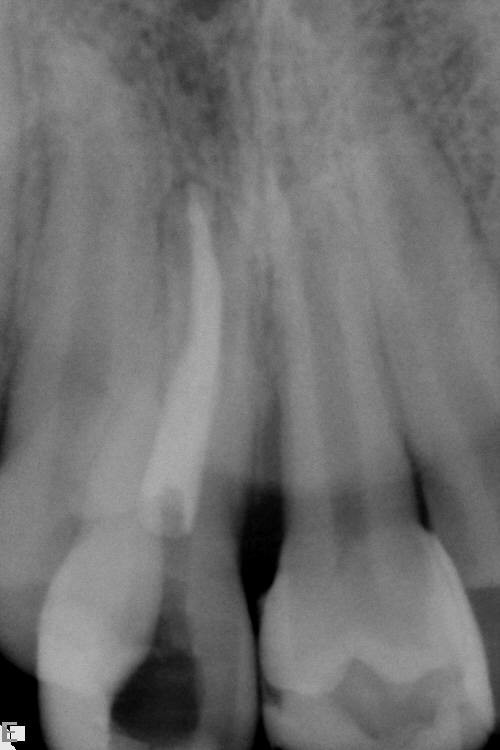

Injury to the inferior alveolar nerve is less common but harder to manage. The nerve may be directly injured by the needle during the injection of local anaesthetic or may be crushed by the tooth root during elevation. Rarely the roots of the tooth may surround and encase the nerve so that elevation is unavoidable. Clues to this injury can be seen on the radiograph and when the tooth will not elevate easily (it actually feels as if it is attached by a rubber band).

Increasing availability of cone beam computed tomography scans (CBCT) can be useful in assessing lower third molars whose roots are in close proximity to the inferior alveolar nerve and helping to determine the risk of neurosensory disturbance. If such cases are identified, a decision may be made to remove the crown of the tooth only (coronectomy; see above).